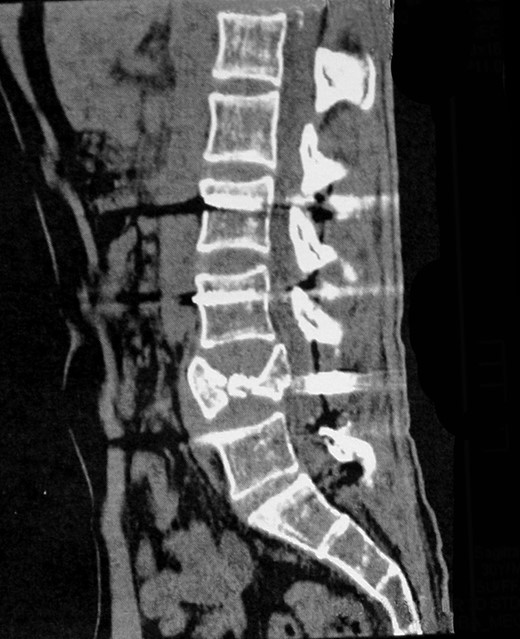

A previously healthy 30-year-old man presented with sudden and intense back pain after lifting a heavy object. Radiological investigation demonstrated an L4 burst fracture with presence of bone fragments in the spinal canal (Fig. 1). Clinical examination was normal except for a mild left foot numbness. His routine laboratory assessment revealed hypochromic microcytic anemia.

Computed tomography scan of the lumbar spine showing an L4 burst fracture.